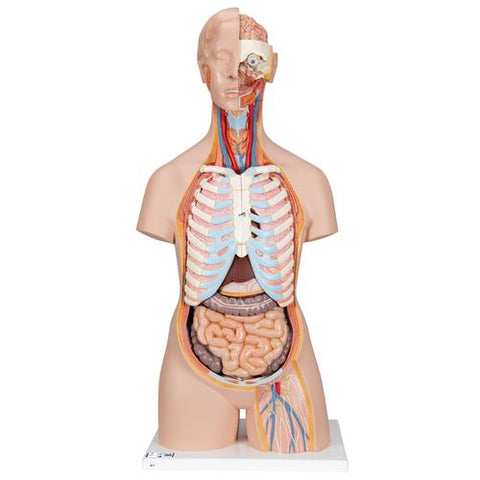

Classic Unisex Human Torso Model with Open Back, 21 part - 3B Smart Anatomy

This classic torso is hand-painted true to detail and made of high-quality plastic. All 3B torsos are also developed and modeled in Germany. This human torso has the unique feature of an open neck and back section going from the cerebellum to the coccyx. Vertebrae, intervertebral discs, spinal cord, spinal nerves, vertebral arteries, and many other features are represented in detail is this detailed replica of the human anatomy.

The features and removable parts and organs in this unisex torso include:

The features and removable parts and organs in this unisex torso include:

- 7th thoracic vertebra removable

- 6-part head

- 2-part stomach

- Lungs

- 2-part heart

- Liver/gall Bladder

- 4-part intestine

- Kidney half

- Bladder half

- Open back

- Brain

All the organs in this human torso are hand painted for a quality product. This great human anatomy educational tool and makes learning the location of the human organs easy. It is also supplied with the 3B Torso Guide.